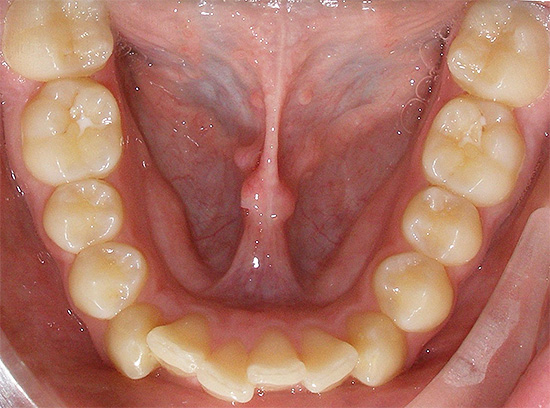

- Affollamento dei denti: questa malocclusione si verifica quando le dimensioni dei denti e degli archi dentali non corrispondono. Circa il 60% dei bambini nella popolazione europea mostra un certo grado di affollamento. In una tale situazione, la perdita di un dente permanente o temporaneo può causare lo spostamento dei denti vicini nell'area del difetto per riempire il vuoto. L'affollamento dei denti inferiori nell'adolescenza è principalmente dovuto alla saggezza dei denti e alla pressione che esercitano sulla dentatura.